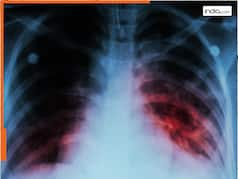

Can A Mother With Tuberculosis Breastfeed The Baby: टीबी एक गंभीर कॉन्टेजियस बीमारी है, जो हवा के जरिए फैलती है, जब किसी को फेफड़ों की टीबी होती है, तो उसके खांसने, छींकने या बात करने से बैक्टीरिया हवा में फैल सकते हैं और दूसरों को इन्फेक्टेड कर सकते हैं. ऐसे में अक्सर ये सवाल उठता है कि क्या टीबी से ग्रसित मां बच्चे को स्तनपान करा सकती है? आइए इसका जवाब डॉ. आस्था दयाल ( डायरेक्टर – आब्सटेट्रिक्स और गायनेकोलॉजी , सीके बिरला हॉस्पिटल गुरुग्राम) से जानते हैं.

डॉ. आस्था दयाल ने बताया कि अगर मां को फेफड़ों की एक्टिव टीबी है और उसका इलाज शुरू नहीं हुआ है, तो बच्चे को इन्फेक्शन का खतरा हो सकता है. इसलिए ऐसी स्थिति में हम आमतौर पर कुछ दिनों के लिए मां को बच्चे से अलग रहने की सलाह देते हैं, लेकिन अगर मां का इलाज शुरू हो गया है और वह दवाएं ले रही है, तो वह डॉक्टर की सलाह से स्तनपान जारी रख सकती है.

टीबी का इन्फेक्शन स्तन के दूध से नहीं फैलता है. अगर मां का इलाज चल रहा है और वह प्रॉपर दवाएं ले रही है, तो शिशु को स्तनपान कराने में कोई खतरा नहीं होता, लेकिन अगर मां को अभी इलाज शुरू नहीं हुआ है या उसे फेफड़ों की एक्टिव टीबी है, तो बच्चे को इन्फेक्शन से बचाने के लिए कुछ सावधानियां बरतनी चाहिए.